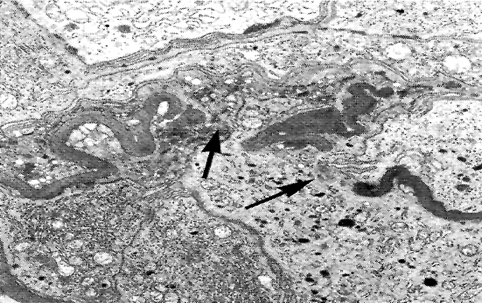

1. 轻微病变性肾小球肾炎

轻微肾小球病变 (minimal change disease) 也称轻微病变性肾小球肾炎(minimal change glomerulonephritis),是一种常见的肾小球疾病,病理特点是光镜下肾小球无明显变化,电镜下肾小球上皮细胞足突融合(如下图),临床特点是大量蛋白尿或肾病综合征。好发于儿童和青少年。

(电子显微镜下可见:肾小球上皮细胞足突融合)

(1)病理变化 :光镜下肾小球无病变或仅见局灶节段性轻度异常。近端肾小管上皮细胞内可见脂滴空泡,故又称脂性肾病(lipoid nephrosis)。

免疫荧光: 肾小球内无免疫球蛋白和补体沉积。

电镜 肾小球基底膜和系膜无显著变化,肾小球内无电子致密沉积物,主要变化是肾小球上皮细胞足突融合,故有人称之为足突病(foot process disease)。

(2)临床表现与预后 :临床上表现为肾病综合征。蛋白尿发生认为与肾小球基底膜所带的负电荷减少有关。负电荷减少有利于带负电荷的血浆蛋白通过毛细血管壁漏出。肾小球无明显炎症,病变轻微,故一般无血尿及高血压,肾功能无损害。糖皮质激素治疗效果好。